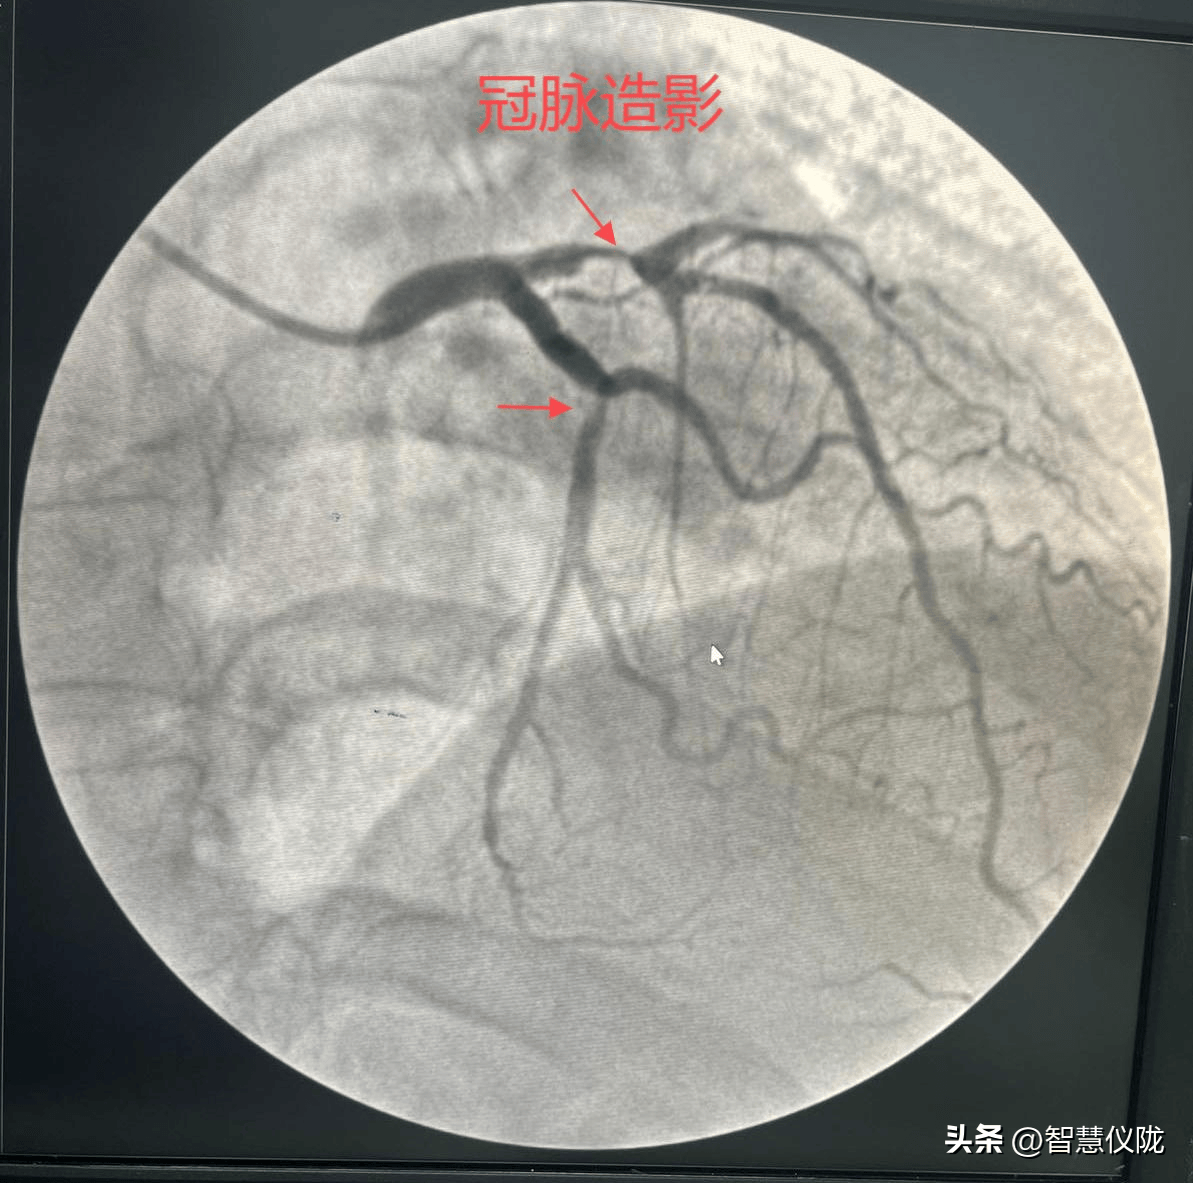

医学科普# 冠状动脉造影提示:前降支近段完全闭塞,开通血管,冠状动脉

图左:11月25日,术中冠脉造影显示,杨先生的左冠状动脉回旋支闭塞.